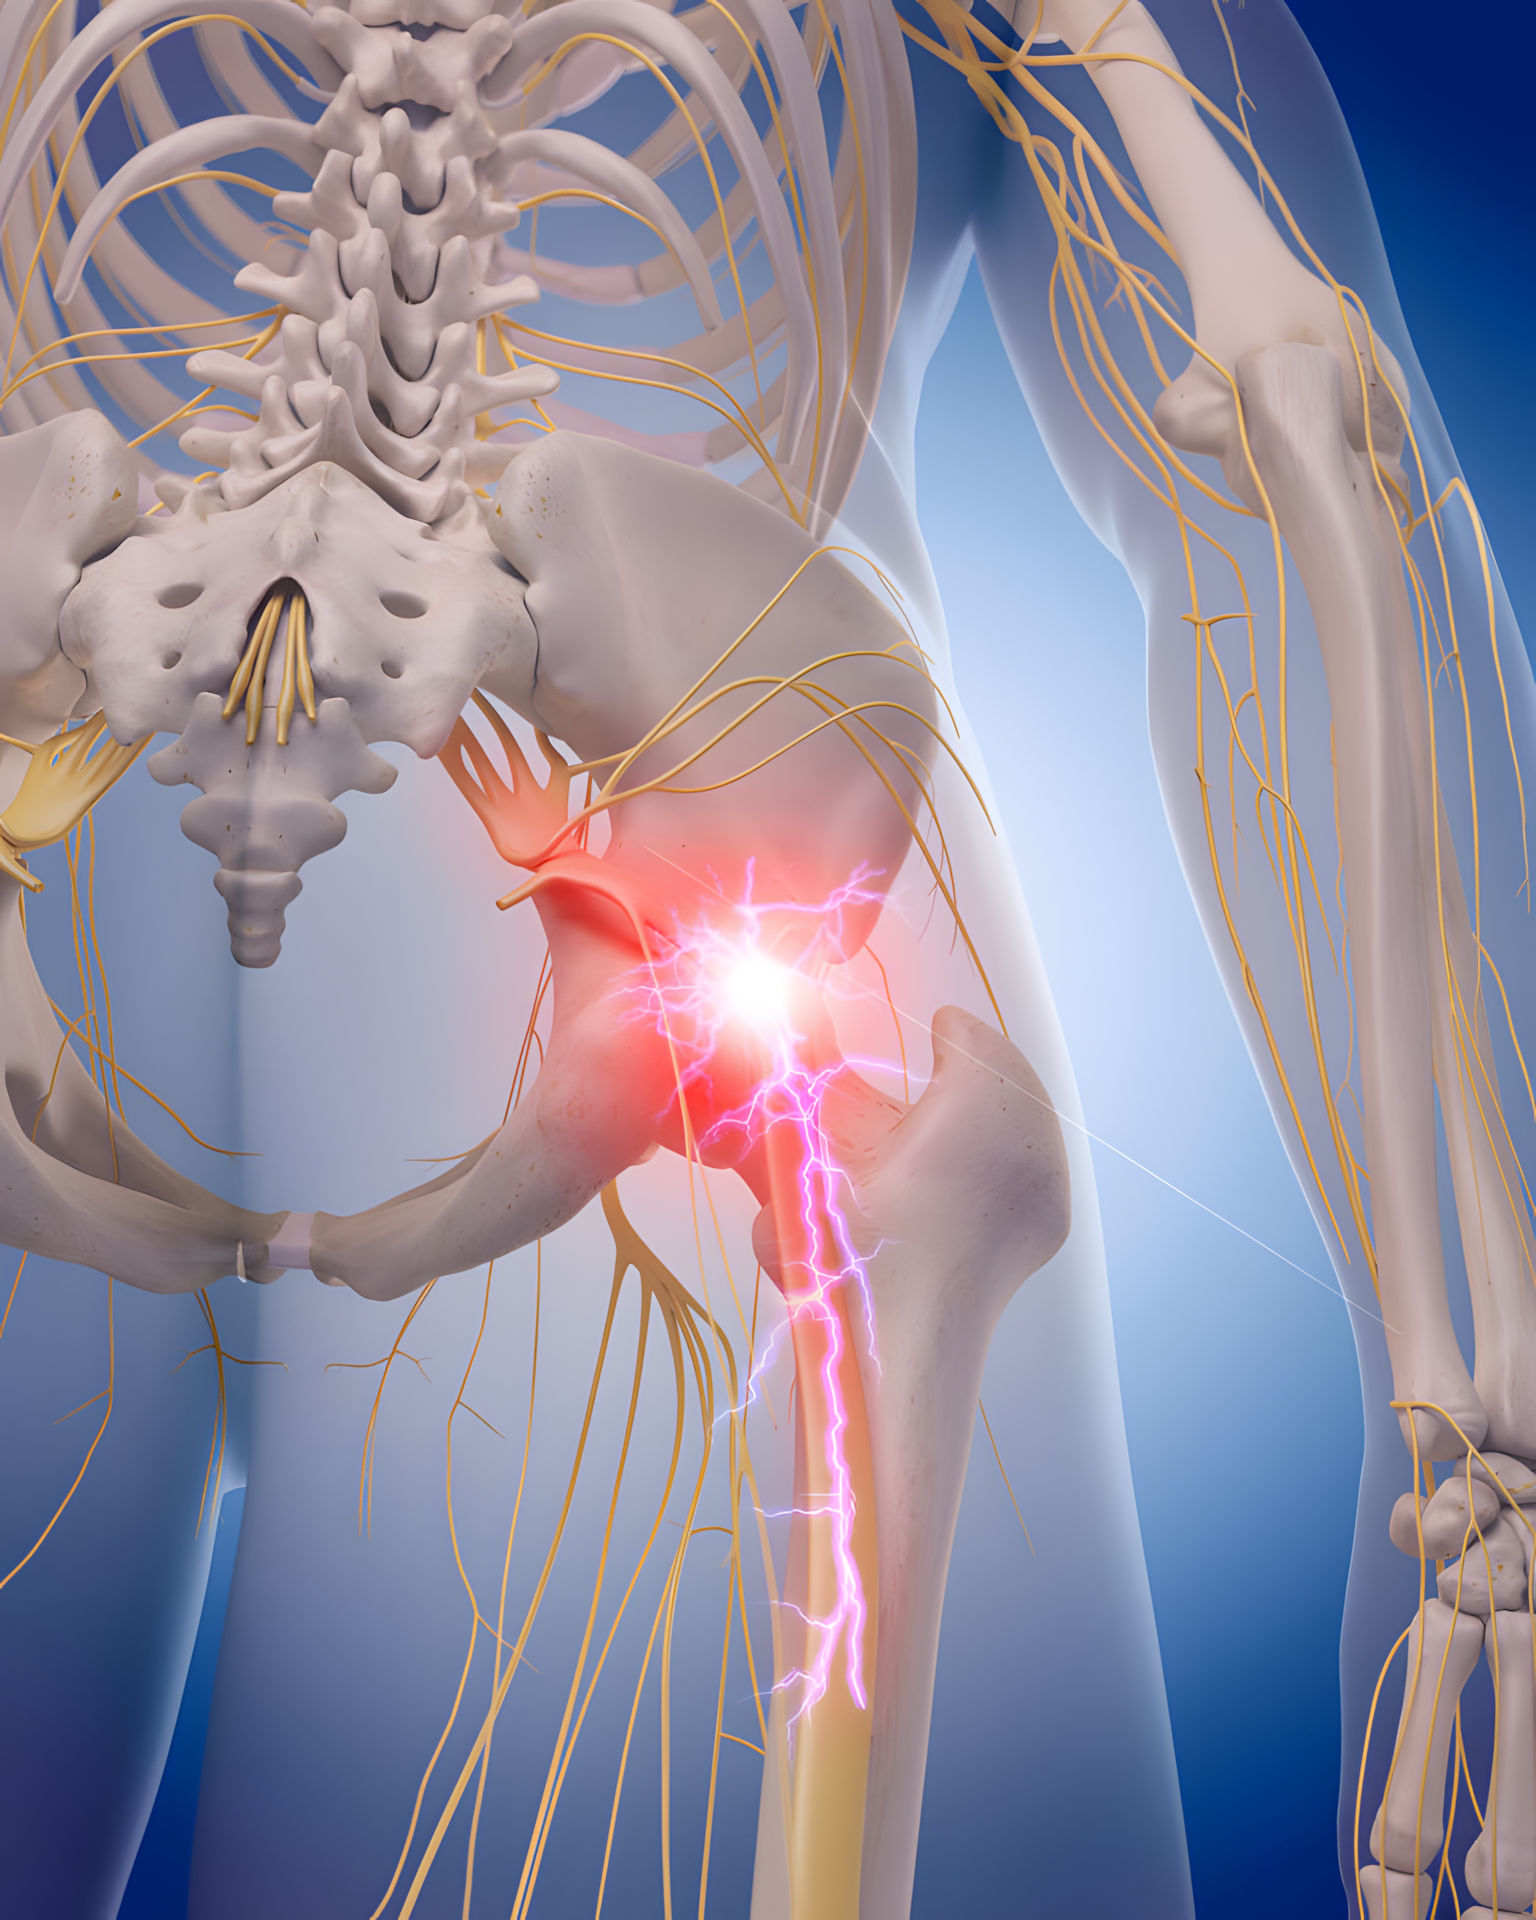

Ból nerwów, w tym ból związany z rwą kulszową, należy do jednych z najbardziej uciążliwych dolegliwości, z jakimi zmagają się pacjenci. Może być piekący, przeszywający, promieniujący i trudny do opanowania, a jego nasilenie często wpływa na codzienne funkcjonowanie, sen oraz ogólną jakość życia. Dla wielu osób znalezienie skutecznej metody leczenia okazuje się procesem wymagającym czasu, cierpliwości i indywidualnego podejścia.

Naturalne suplementy diety zyskały w ostatnich latach dużą popularność wśród osób poszukujących alternatywnych lub wspomagających metod łagodzenia bólu nerwowego. Często wymieniane są preparaty zawierające witaminę B12, imbir, beta-karoten, magnez czy cynk.